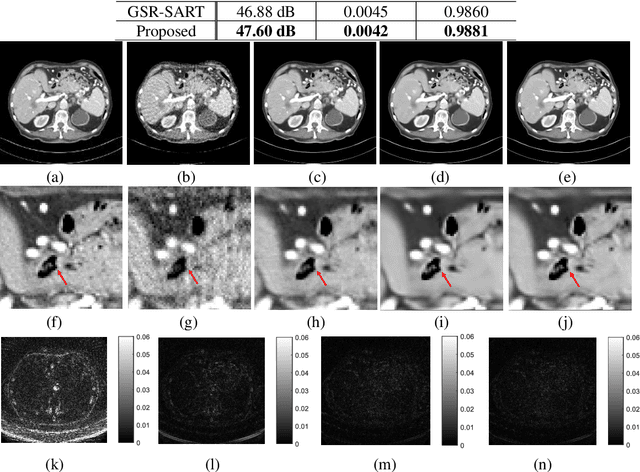

Abstract:Compressive sensing (CS) based computed tomography (CT) image reconstruction aims at reducing the radiation risk through sparse-view projection data. It is usually challenging to achieve satisfying image quality from incomplete projections. Recently, the nonconvex ${{L_ {{1/2}}}} $-norm has achieved promising performance in sparse recovery, while the applications on imaging are unsatisfactory due to its nonconvexity. In this paper, we develop a ${{L_ {{1/2}}}} $-regularized nonlocal self-similarity (NSS) denoiser for CT reconstruction problem, which integrates low-rank approximation with group sparse coding (GSC) framework. Concretely, we first split the CT reconstruction problem into two subproblems, and then improve the CT image quality furtherly using our ${{L_ {{1/2}}}} $-regularized NSS denoiser. Instead of optimizing the nonconvex problem under the perspective of GSC, we particularly reconstruct CT image via low-rank minimization based on two simple yet essential schemes, which build the equivalent relationship between GSC based denoiser and low-rank minimization. Furtherly, the weighted singular value thresholding (WSVT) operator is utilized to optimize the resulting nonconvex ${{L_ {{1/2}}}} $ minimization problem. Following this, our proposed denoiser is integrated with the CT reconstruction problem by alternating direction method of multipliers (ADMM) framework. Extensive experimental results on typical clinical CT images have demonstrated that our approach can further achieve better performance than popular approaches.